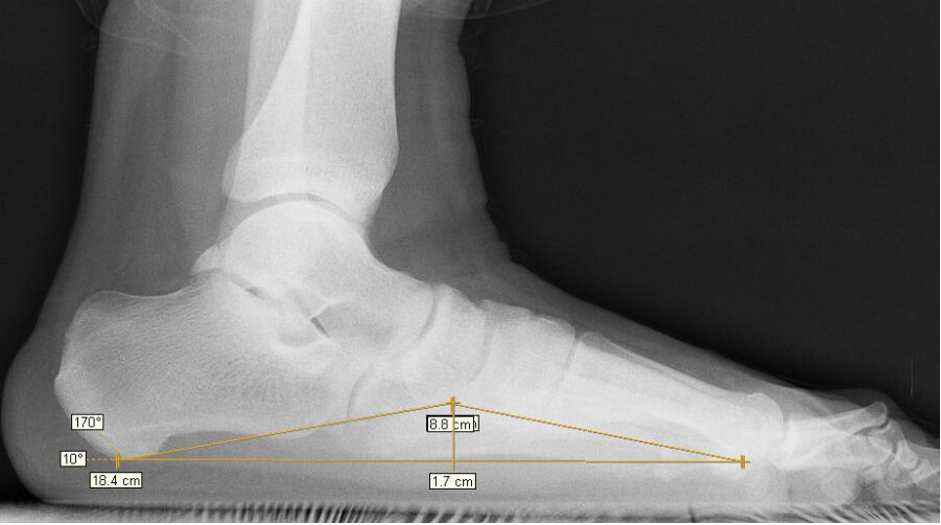

Для определения степени болезни врач назначает рентгенографию. Снимки позволяют точно определить детали деформации. Так, при 1 степени высота свода должна быть не меньше 24 мм. Оценивается угол свода. Приемлемый диапазон — от 131 до 140°. Если есть превышения, то это уже 2 степень плоскостопия.

Сложнее определить категорию годности при комбинированной форме заболевания. Особенно если у продольного и поперечного плоскостопия разные степени выраженности. В этом случае врач ориентируется только на угол свода. При поперечном плоскостопии измеряют промежуток между 1 и 2 плюсневыми костями. Для первой степени допустим диапазон от 10 до 12°. Если уже видна деформация большого пальца, то ее тоже измеряют. Для первой степени диапазон составляет от 15 до 20°.